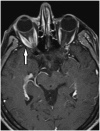

Dawson Fingers

Multiple sclerosis has a wide array of radiological findings, and many of these have their own signs. Demyelinating plaques with a perpendicular course, adjacent to the body of the lateral ventricle, present as hyperintensities on T2WI (Fig. 7) (11). They are called Dawson’s fingers and are are considered to be a relatively specific sign for MS.

caption a8Dawson fingers.